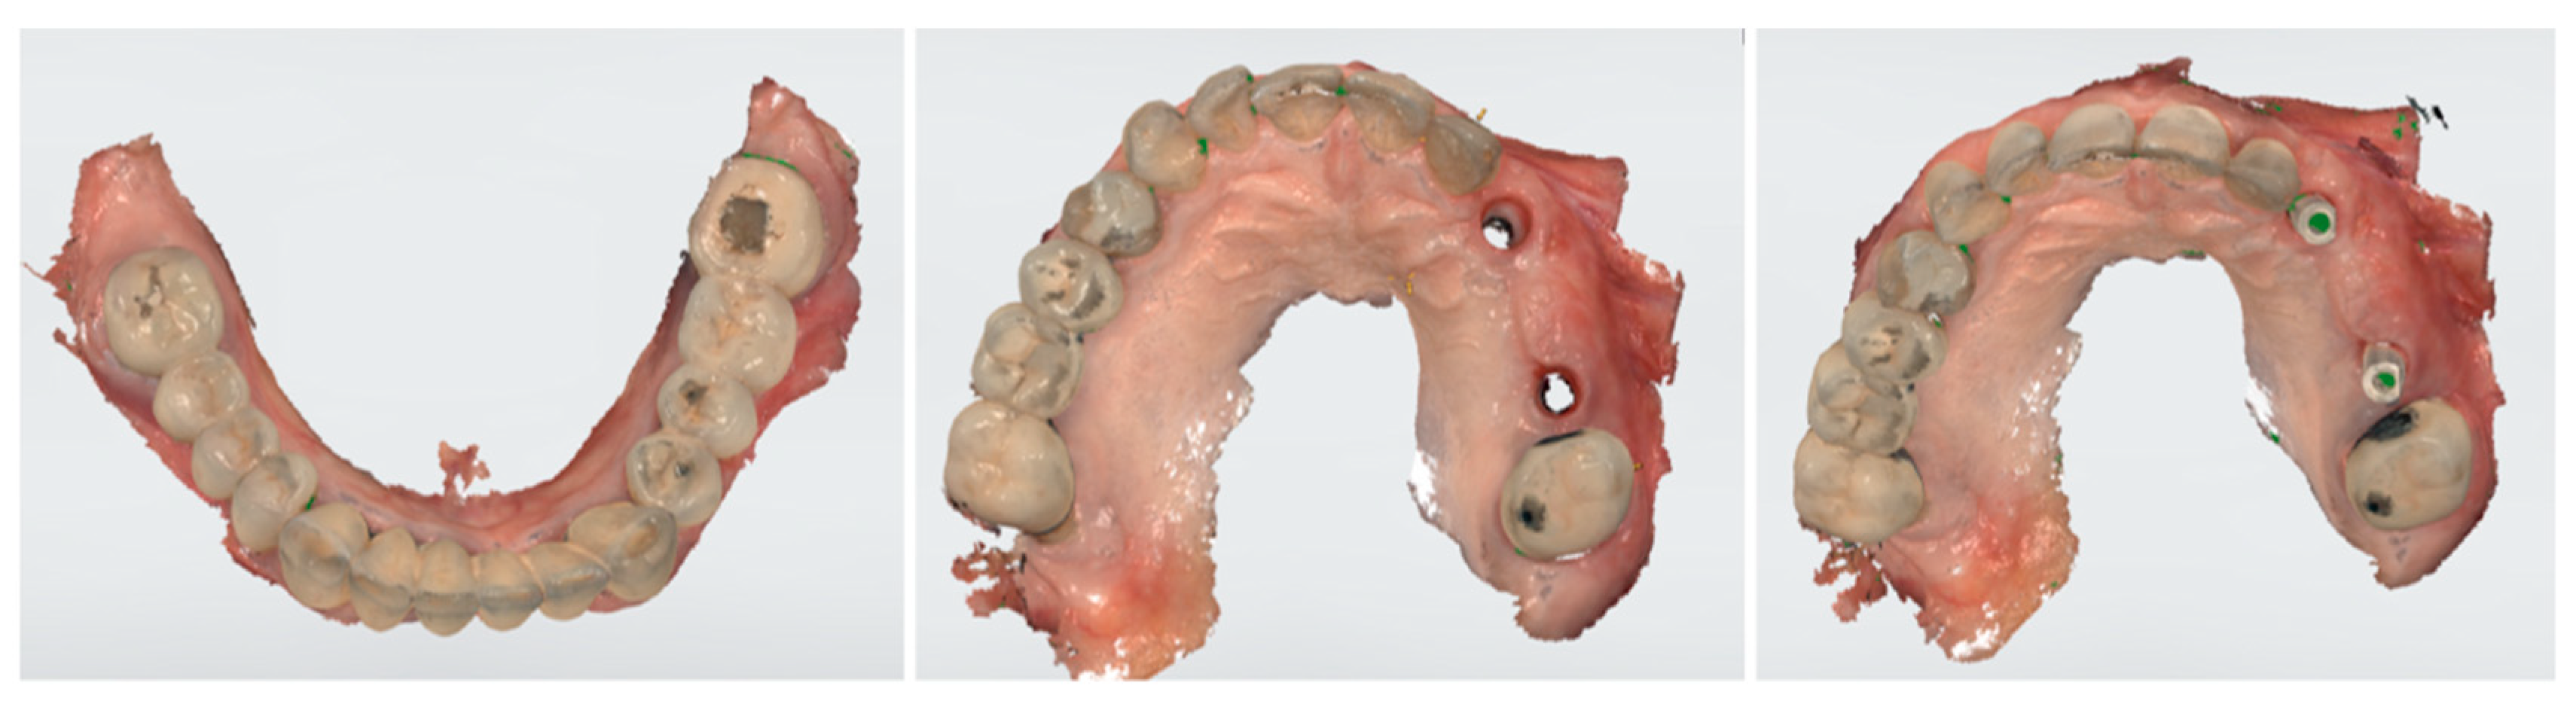

After another 3 months, following the verification of osseointegration, optical impressions were taken for the completion of the final prosthesis (Figure 4). After normal prosthetic phases, a screw retaining a three-unit bridge made of monolithic zirconia was applied (Figure 5). The occlusion and soft tissue compression were verified. After delivery, the occlusal function and soft tissue stability were monitored in the following months.

Figure 4.

Optical impressions for completion of the final prosthesis.